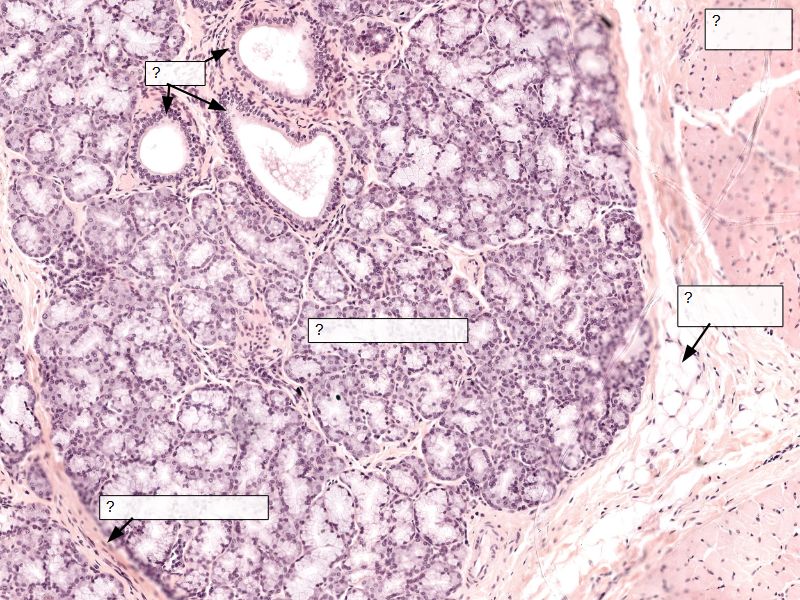

Fill in all the missing labels, and assess as you move through the slides. Answers on the down slide. It is important to do this using pen and paper, and not just glance through the images.